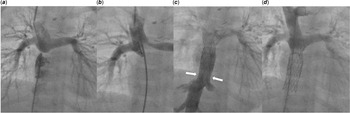

After approval of the local ethics committee, a non-restrictive, dilatable banding of the inferior vena cava with a diameter of 12 mm was placed during the operation for the superior cavopulmonary connection. At the age of 2 years, the patient (weight 12.7 kg) was scheduled for the intervention of Fontan. The mean pulmonary artery pressure was 9 mmHg, and the transpulmonary gradient was 2 mmHg, indicating favourable haemodynamic conditions for total cavopulmonary connection completion. The procedure was performed under real-time guidance of a biplane fluoroscopy system. The right pulmonary artery was punctured with a transseptal needle from the right groin through the roof of the right atrium (Figure 1a,b). Subsequently, a long sheath (12F) was introduced without the need for balloon dilatation. A 0.035’ Amplatz Ultra Stiff ™ (Boston Scientific, Marlborough, MA, USA) guidewire was used to establish and maintain the circuit throughout the procedure, ensuring adequate support for stent delivery and deployment. A Fontan circulation was established (Figure 1c, d), using two overlapping covered stents (Optimus, AndraTech GmbH, Koblenz, Germany) on 14 mm balloons (BiB, NuMed, Hopkinton, NY, USA) anchored in the banded inferior vena cava and in the puncture site of the pulmonary artery, respectively. The first stent, measuring 33 mm, was deployed in the inferior vena cava. The second stent, 38 mm in length, was positioned to bridge the connection toward the pulmonary arteries. Both stents were post-dilated to achieve full expansion and optimal sealing. During the implantation, repeated contrast injections were used to identify the proximal and distal landing zones, ensuring avoidance of the hepatic veins and unobstructed flow to the pulmonary arteries. During the whole procedure, the patient was spontaneously breathing and haemodynamically stable. She was monitored in the ICU for one night. The postinterventional recovery was uneventful under 0,3 mg/kg/min milrinone and gentle volume substitution. Lifelong anticoagulation with warfarin was initiated, following the standard approach for all Fontan patients in our clinic. The patient was discharged home after 7 days. The follow-up period was 17.1 months. During this time, the child remained in a very good clinical condition. The next catheterisation is planned 48 months after the intervention to re-dilate the 14 mm stents to a larger size.

Figure 1. ( a ) Initial anatomy showing the proximity of the roof, the right atrium and the lower part of the right pulmonary artery. ( b ) The right atrium and pulmonary artery are connected by a puncture with a transseptal needle. ( c ) Creation of an intracardiac conduit using two covered stents between the banded IVC and the right pulmonary artery. ( d ) Injection into the superior caval vein showing unobstructed flow into both pulmonary arteries.

Figure 1. (a) Initial anatomy showing the proximity of the roof, the right atrium and the lower part of the right pulmonary artery. (b) The right atrium and pulmonary artery are connected by a puncture with a transseptal needle. (c) Creation of an intracardiac conduit using two covered stents between the banded IVC and the right pulmonary artery. (d) Injection into the superior caval vein showing unobstructed flow into both pulmonary arteries.